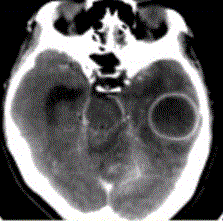

问题 患者女,26岁,头痛、低热10d余,既往有左侧慢性中耳炎病史。CT表现如下图。 关于脑脓肿的诊断要点,不正确的是

选项 A.常合并化脓性脑膜炎 B.颞叶最常见,约占40% C.多发者高达70% D.单发占70% E.病理学和影像学上可分为炎症期和脓肿形成期

答案 C